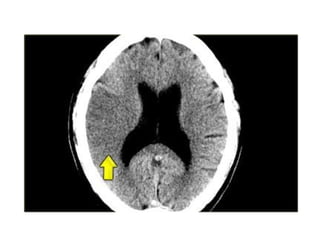

2.Obscuration of the lentiform

nucleus

• Obscuration of the lentiform nucleus, also

called blurred basal ganglia, is an

important sign of infarction.

It is seen in middle cerebral artery

infarction and is one of the earliest and

most frequently seen signs.